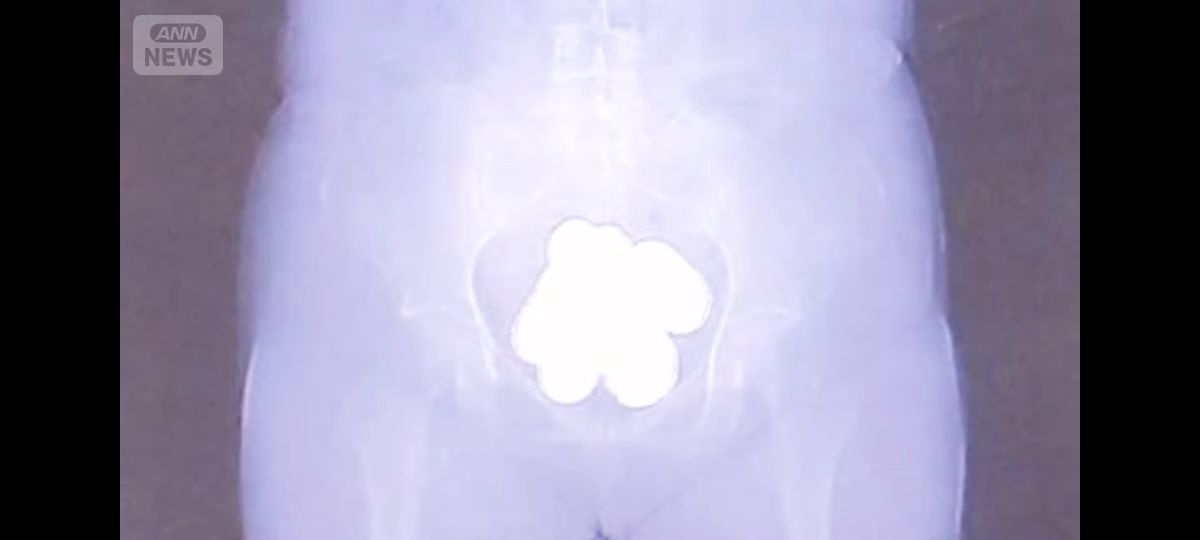

- 成田税関によりますと、今年1月から3月までに成田空港で航空機の乗客による金の密輸を33件、およそ46キロを摘発したということです。

そのうち、30件は金を粉状にして密輸していました。

量はおよそ45キロ、12億円相当です。30件のうち22人が女で、粉状の金は避妊具などに入れて体の中に隠す手口で持ち込まれていました。

- レントゲン写真卵みたい